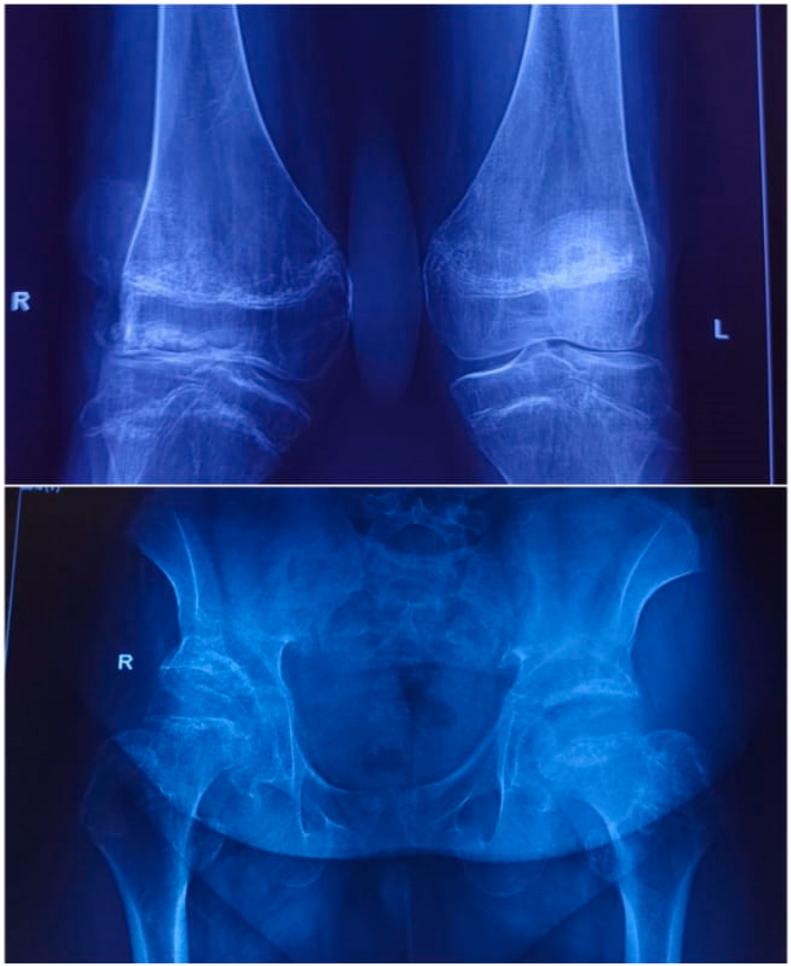

This case presents a unique incidental finding of skeletal dysplasia in a fifty-year-old male patient who presented with osteoarthritis. Eventual workup uncloaked the presence of cleidocranial dysplasia and spondyloepiphyseal dysplasia. The patient in this case had both dysplasias at the same time.

Cleidocranial dysplasia and Spondyloepiphyseal dysplasia are two uncommon autosomal dominant dysplasia's that are often diagnosed in early life and can have serious consequences, including death. It is critical to diagnose a child early in life. Radiology findings from a thorough skeletal examination aid in the early detection of numerous dysplasia's, which helps improving quality of life and allowing for effective treatment.

本病例展示了一名50岁男性骨关节炎患者骨骼发育异常这一独特的偶然发现。最终检查揭示了锁骨颅骨发育不全和脊椎骨骺发育不良的存在。该病例患者同时患有这两种发育异常。

锁骨颅骨发育不全和脊椎骨骺发育不良是两种罕见的常染色体显性发育异常,通常在生命早期被诊断出来,可能会产生严重后果,包括死亡。在儿童生命早期进行诊断至关重要。全面骨骼检查的影像学结果有助于早期发现多种发育异常,这有助于提高生活质量并实现有效治疗。